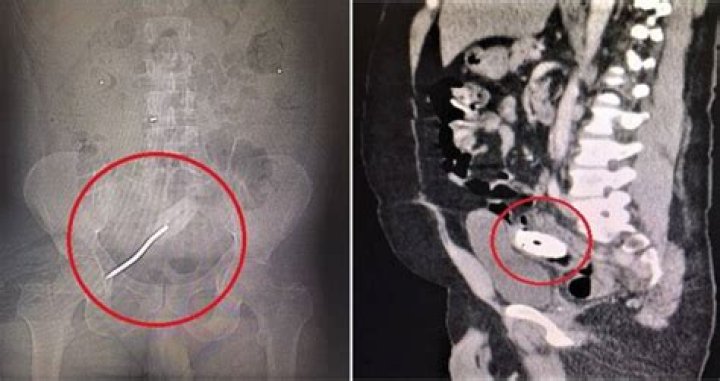

Youssef Shaban et alA CT scan showed that the Florida man had a screwdriver stuck inside his rectum.

The man told doctors he’d been experiencing pain in his abdomen and pelvis for a week. A CT scan quickly revealed the cause: a full-sized screwdriver lodged inside his rectum. The tool, which was almost eight inches long, was buried deep enough that it had pierced his large intestine.